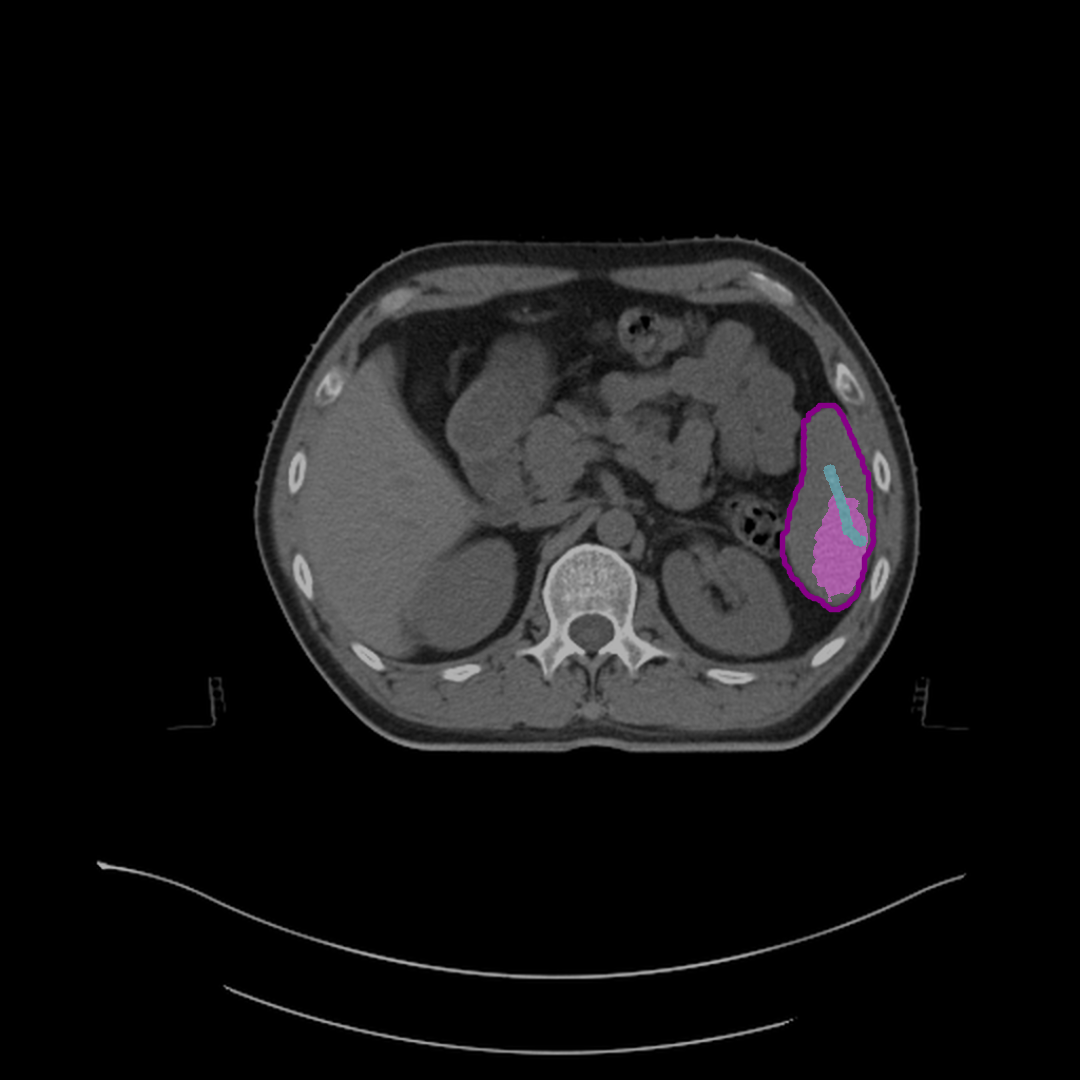

Refer to caption

(a) Initial predicted mask.

(b) Mask after half correction.

(c) Mask after full correction.

Figure 4: Steps to correct segmentation masks for various abdominal organs, such as the spleen, left kidney, and liver, on different CT slices. Each subfigure shows the outline of reference segmentation contours, the predicted segmentation mask, and gaze points (blue) used for predictions based on gaze.